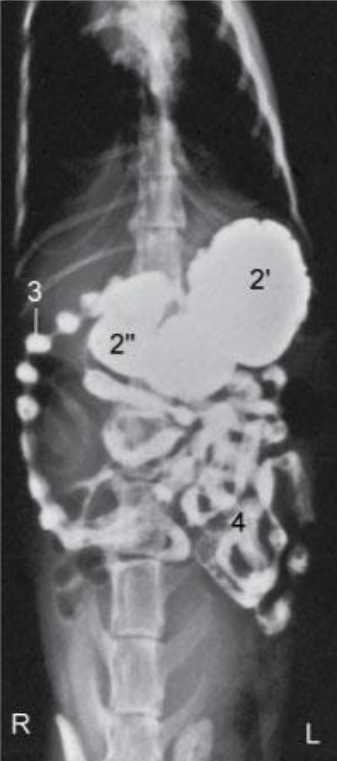

Runs caudally (right side) – Descending duodenum- level of tuber coxae- makes a U- turn –runs obliquely-craniosinistrally (leftside)- continues as the ascending duodenum